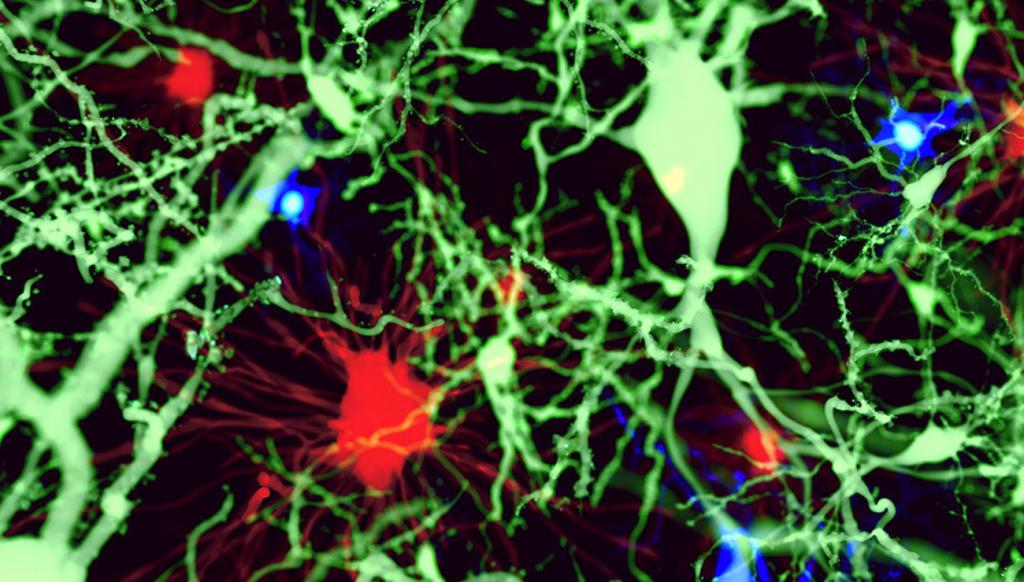

Les chercheurs de l'Université de Virginie ont en effet découvert que le parasite connu sous le nom de Toxoplasma gondii est contrôlé par les microglies. Les microglies, aussi appelées "microgliocytes", ou encore "cellules de Hortega", sont une population de cellules macrophages que l'on retrouve dans le système nerveux central (cerveau, moelle épinière et rétine), et qui forment la principale défense immunitaire active grâce à ses capacités phagocytaires. Pour être plus clair, ce sont un peu les éboueurs de notre organisme, capables de manger ou détruire des microbes et des particules étrangères à l'organisme.

Le fonctionnement des microglies.

Comprendre le rôle des microglies est absolument essentiel puisqu'il s'agit des cellules immunitaires présentes à l'intérieur du cerveau. La découverte effectuée par l'équipe de chercheurs de Virginie met le doigt sur la façon dont les microglies demandent de l'aide en cas de besoin, et cette découverte pourrait bien, à terme, permettre de trouver des solutions pour lutter plus efficacement contre les lésions cérébrales, les maladies neurodégénératives, les AVC, ou encore la sclérose en plaques.